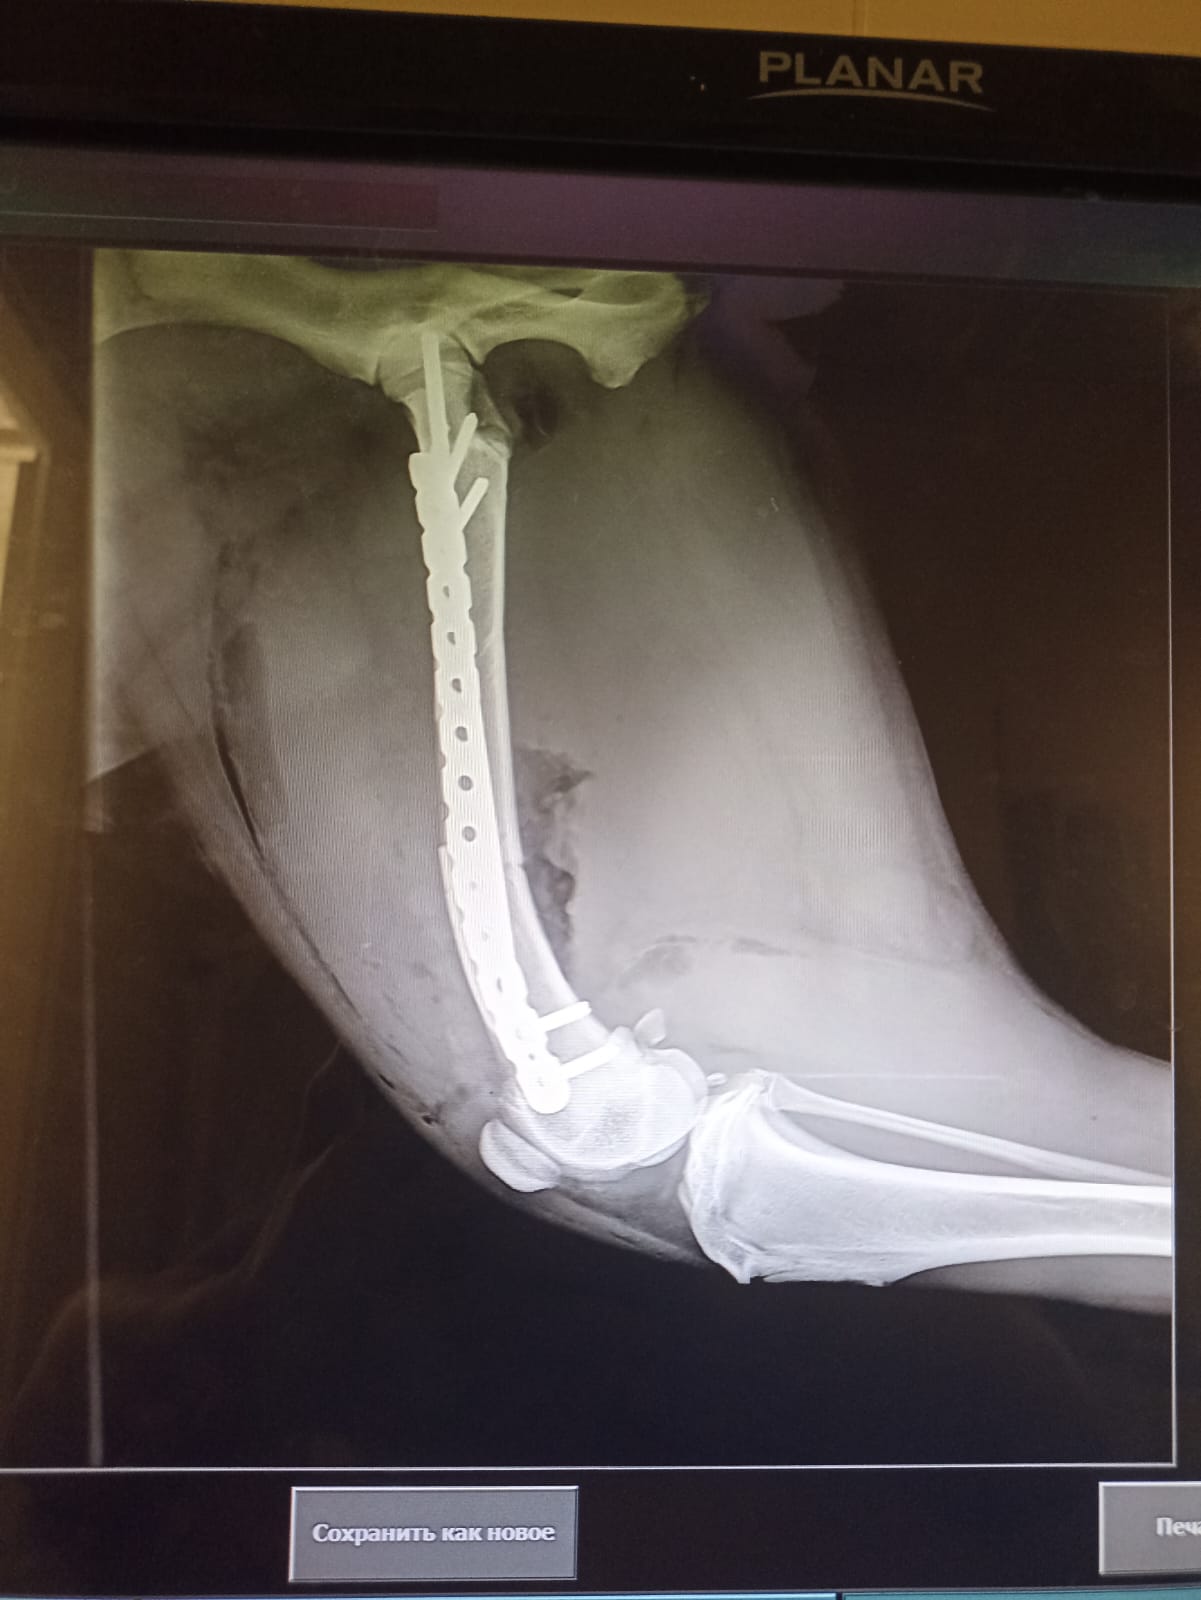

Через 2 недели контрольный рентген и снятие швов.

на 19-е записались на контрольный рентген и снятие швов.